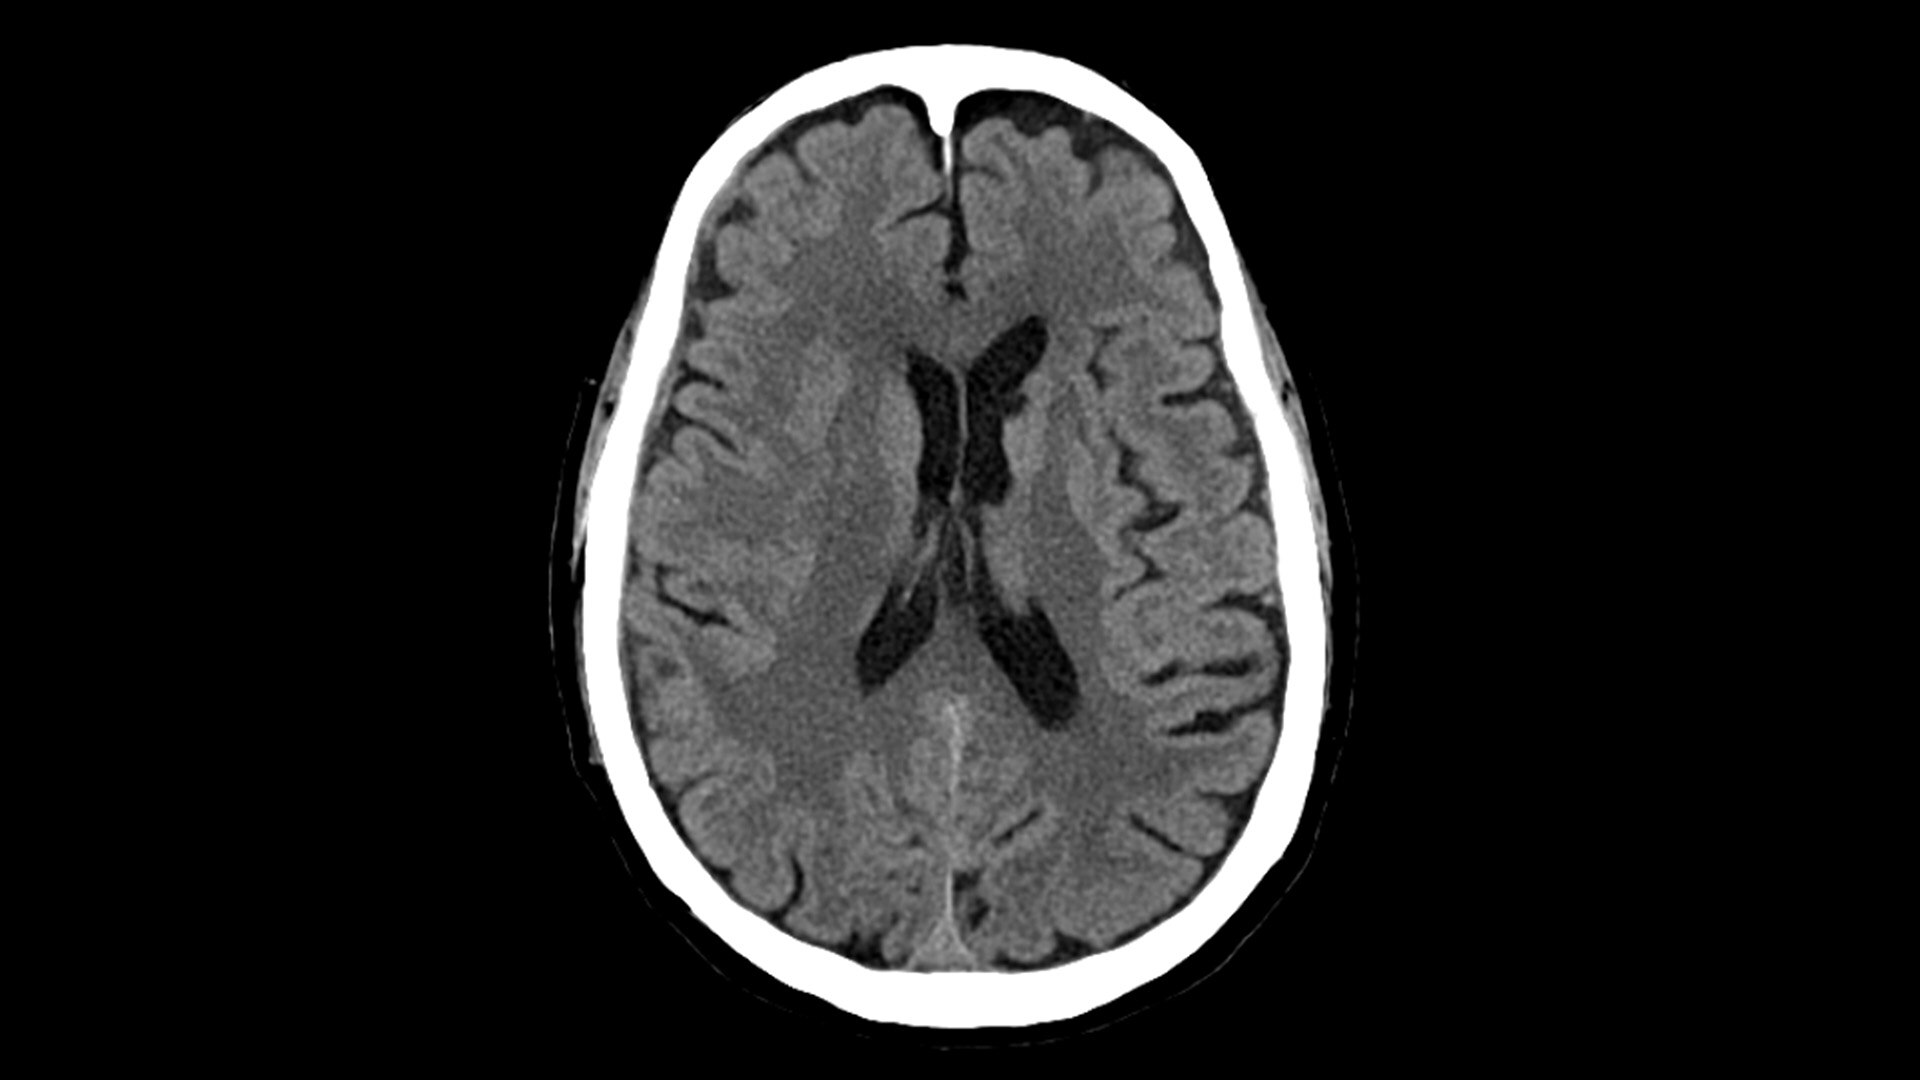

for the realization of the full potential of photon-counting CT in oncology, cardiology, neurology and more.

Photonova Spectra delivers ultra-high-definition imaging with wide coverage, enabling fast acquisition and precise visualization of anatomical structures. Engineered with on-demand spectral imaging available for every scan, it helps to support clinicians in detecting, characterizing, and monitoring disease with confidence and ease.

With ultra-high spatial resolution scanning capability, Photonova Spectra is designed to help you see incredibly fine details, such as coronary plaque delineation, small microvascular vessels and even tiny structures of the inner ear.